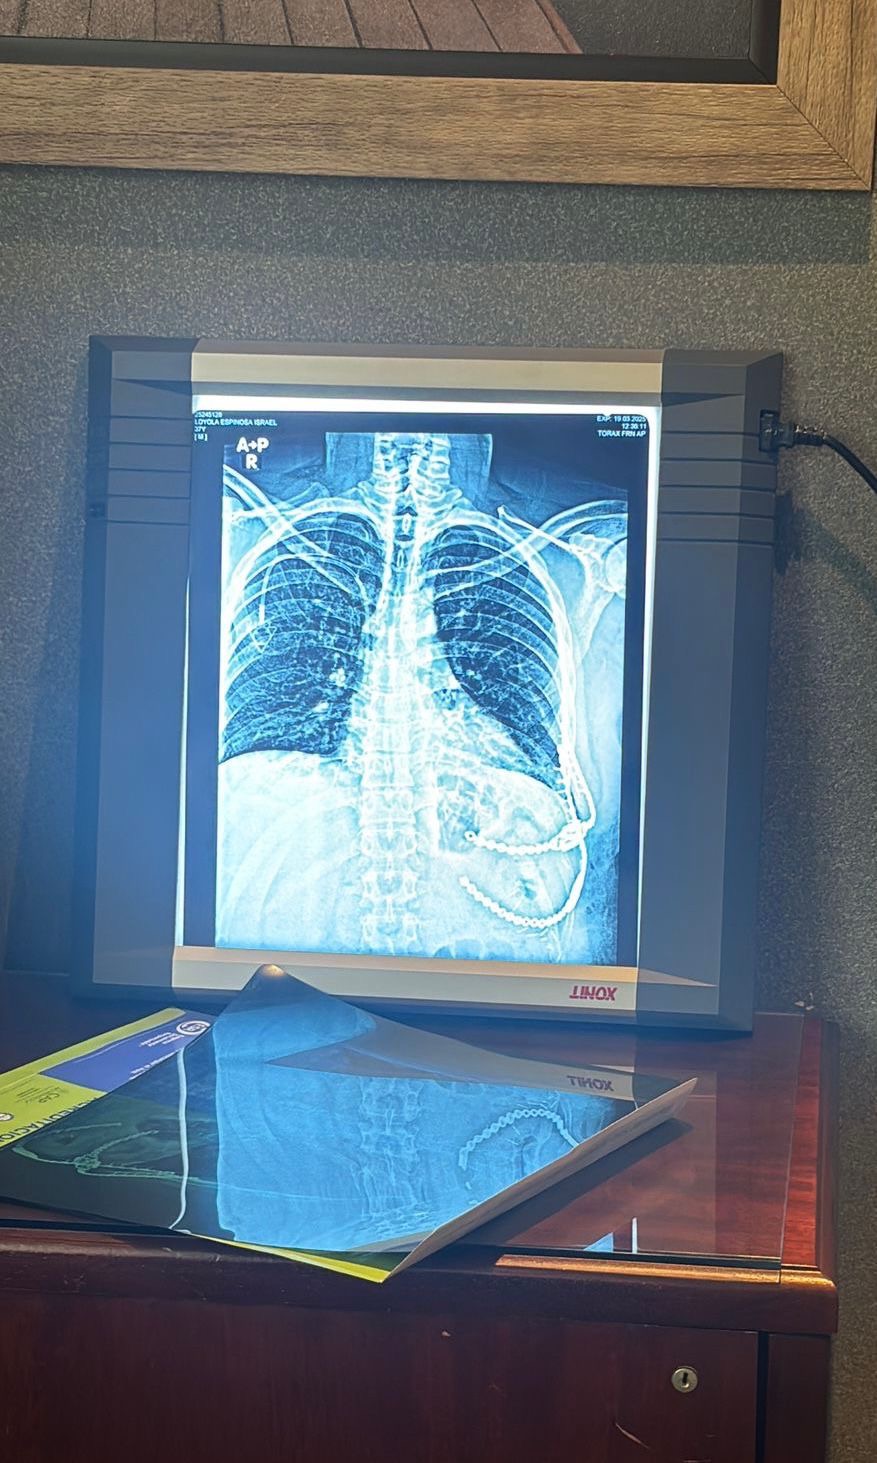

En septiembre del 2024, notó que tenía un abultamiento del lado izquierdo a la altura de las costillas y tras ir con varios médicos y obtener varios diagnósticos (diferentes cada uno) surgió uno más atinado a mediados de octubre del mismo año en el que le pedían una tomografía de contraste. Se contactó al Dr. Alejandro Rojas en la Ciudad de México para una biopsia oncológica para tener un resultado más certero. Primero, le diagnosticaron sarcoma de Ewing, un tumor muy agresivo y de rápido crecimiento, pero una segunda opinión y análisis del Dr. Raúl Mellado, lo diagnosticó con sarcoma sinovial bifásico también agresivo y de rápido crecimiento. A finales de noviembre se debían cumplir un ciclo de quimioterapias con el fin de controlar el avance del mismo para después realizar una intervención para extraer el tumor. Al llegar a ese punto, el sarcoma ya se encontraba en la cuarta etapa de cuatro y empezó a hacer metástasis. La operación estuvo a cargo de la Dra. Francina Bolaños quien dio un diagnóstico favorable.

El tratamiento continúo con 30 sesiones de radioterapia diarias, que en breve, finalizarán para, posteriormente, realizar un estudio PET, o tomografía de emisión de positrones, y continuar así con la rehabilitación de un largo proceso.